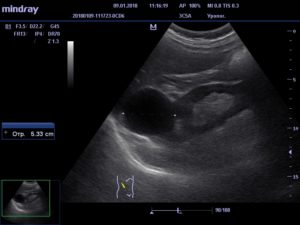

Обычно исследование начинают с проведения рентгена и скрининга. Также делается КТ (компьютерная томография) и пункционная кистография. Чтобы поставить диагноз и назначить эффективное лечение пациенту, применяется УЗИ.

При этом обязательно указывают расположение кисты паренхимы: левой или правой почки. Стадия патологического процесса определяется при помощи ультразвука и проведения МРТ, чтобы выявить такие патологии, как злокачественная киста паренхимы.

Обследование проводят, начав в рентгена с контрастным веществом, скрининга, используют компьютерную томографию. УЗИ-диагностику применяют для постановки диагноза, назначения эффективного лечения.

Локализация образования играет роль: справа, слева располагается киста паренхимы. Степень проблемы — злокачественное образование — определяют ультразвуком, магнитно-резонансной томографией.

При появлении симптомов болезни рекомендуется пройти ультразвуковое обследование, компьютерную или магнитно-резонансную томографию. Лечение назначается с учетом результатов обследования.

Пациентам рекомендовано провести ультразвуковое исследование почек, с помощью которого определяется месторасположение, параметры и структура новообразования. Пациентам назначают компьютерную и магнитно-резонансную томографию. С помощью КТ и МРТ уточняется информация, полученная при ультразвуковом исследовании.